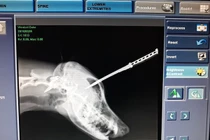

Ngay sau đó, Zeus được chủ nhân đưa vào bệnh viện thú y cấp cứu. Thế nhưng bác sĩ cho biết, rắn san hô là loại rắn cực độc, nọc độc của nó tấn công trực tiếp và phá hỏng hệ hô hấp, không thể cứu. Sang ngày hôm sau, chú chó dũng cảm Zeus vì suy hô hấp mà qua đời.